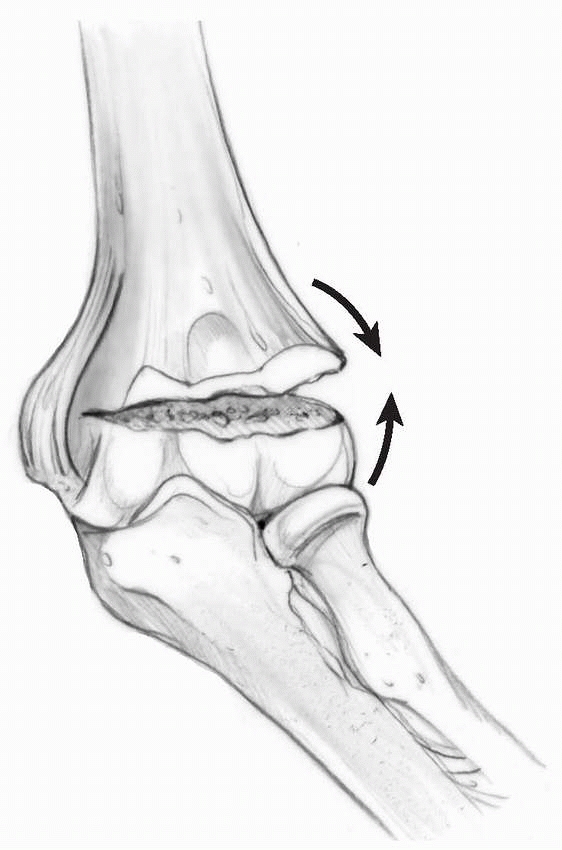

and flexion types, depending on the direction of displacement of the

distal fragment. Extension type fractures are the most common,

accounting for approximately 97% to 99% of supracondylar humeral

fractures.128 They usually are caused by a fall onto the outstretched hand with the elbow in full extension (Fig. 14-1). Most of this chapter discusses extension-type

fractures; flexion-type fractures are discussed separately at the end of the chapter.

FIGURE 14-1 Mechanism of injury—elbow hyperextension. A. Most children attempt to break their falls with the arm extended. With hyperextension, the elbow falls into hyperextension. B. The linear applied force (large arrow) leads to an anterior tension force. Posteriorly, the olecranon is forced into the depths of the olecranon fossa (small arrow). C. As the bending force continues, the distal humerus fails anteriorly in the thin supracondylar area. D.

When the fracture is complete, the proximal fragment can continue moving anteriorly and distally, potentially harming adjacent soft tissue structures such as the brachialis muscle, brachial artery, and median nerve. |